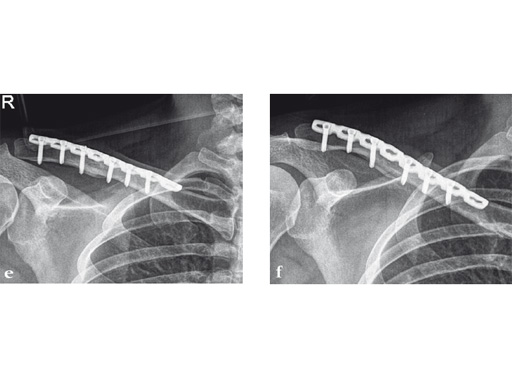

Fig 1 3.5 mm LCP superior clavicle with extension/3.5 mm LCP superior anterior clavicle with extension (short versions of both plates are identical).

Synthes offers a variety of anatomical precontoured plates: the superior, anterosuperior, and anterior clavicle plates. The anterosuperior clavicle plates are also offered with a so-called lateral extension accepting insertion of six 2.7 mm-head locking screws. This also helps to extend the range of indications for even lateral comminuted clavicle fractures. Open reduction and plate fixation can be classically performed via a sabre-cut incision. Alternatively a minimally invasive approach can be used very nicely and is recommended by the authors. The 3.5 mm clavicle hook LCP and the titanium elastic nail complete the repertoire. It is therefore possible to address every midshaft clavicle fracture individually.